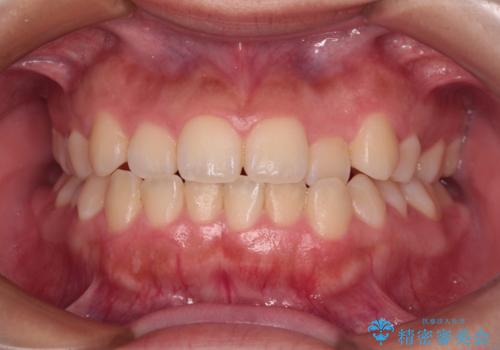

矯正後の後戻りで前歯にガタツキができてしまった インビザラインで改善

前歯のガタツキをインビザラインで改善